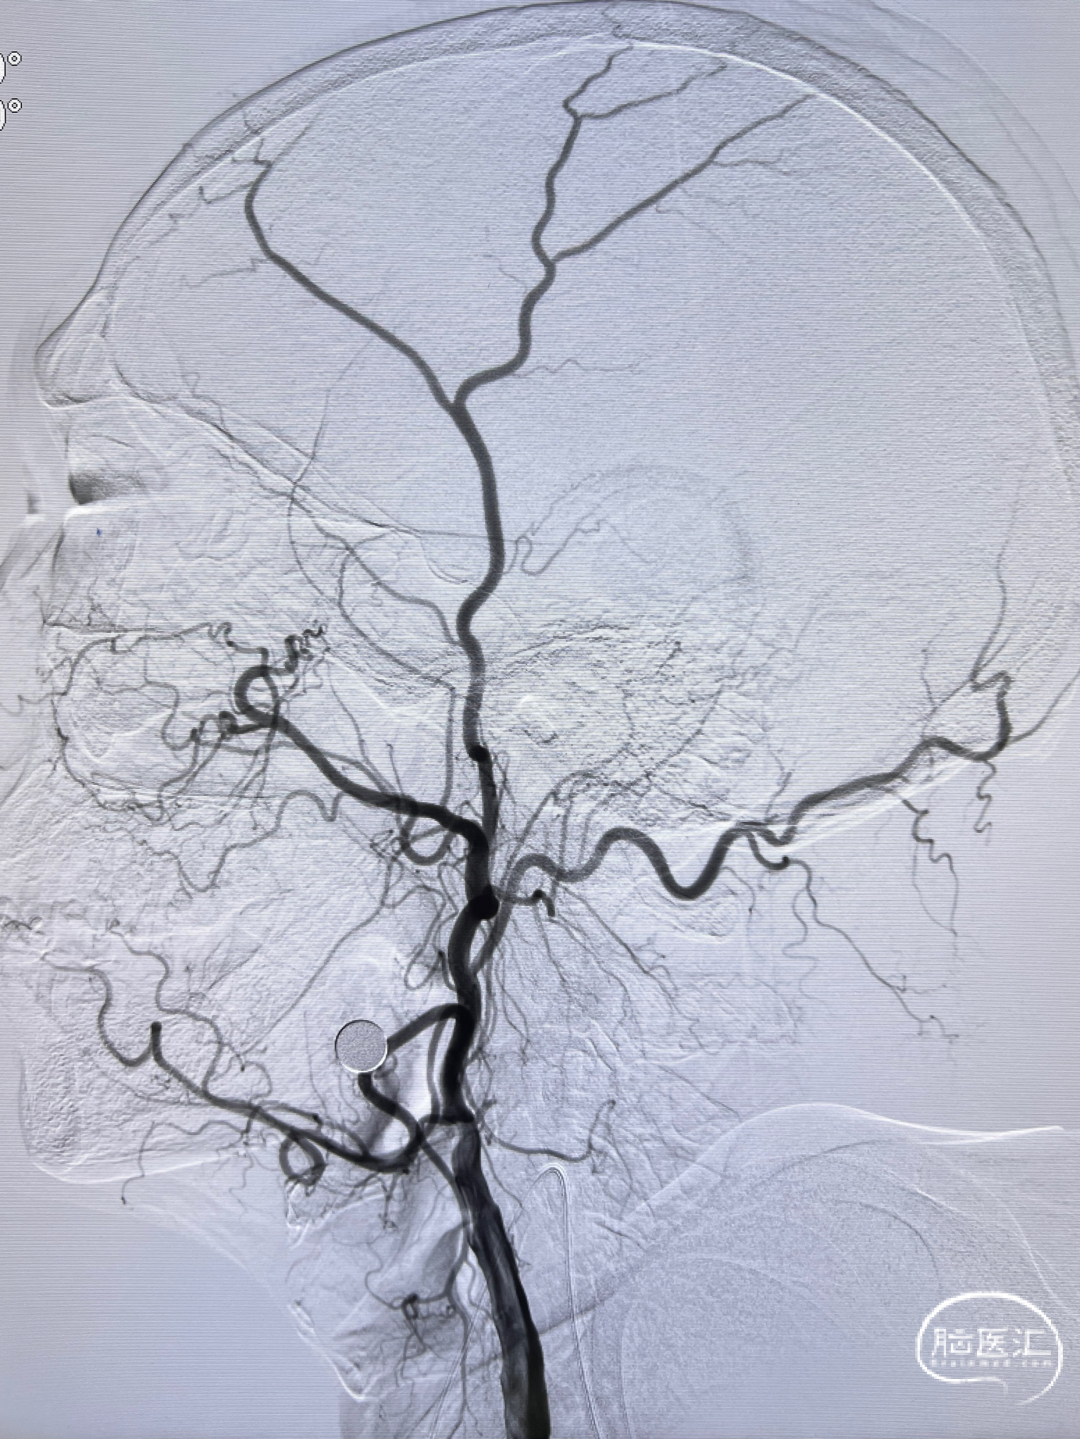

左侧颈内动脉正侧位造影,狭窄解除。

狭窄程度:75%,狭窄长度:16mm

狭窄近端参考血管直径:7.60mm

狭窄远端参考血管直径:6.20 mm